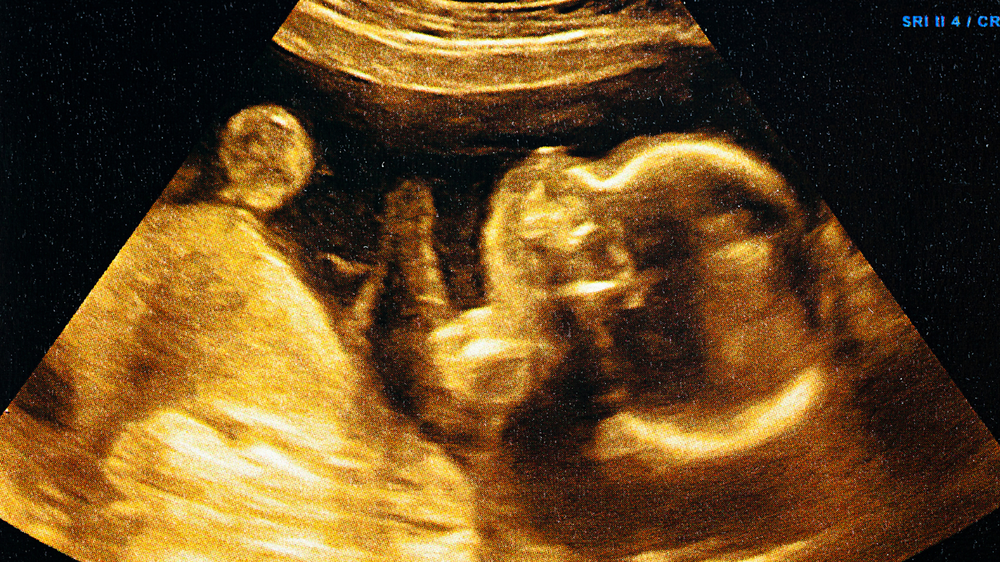

- The earliest movements are often described as flutters, bubbles, or gentle taps.

Emotional Connection with Foetal Movement